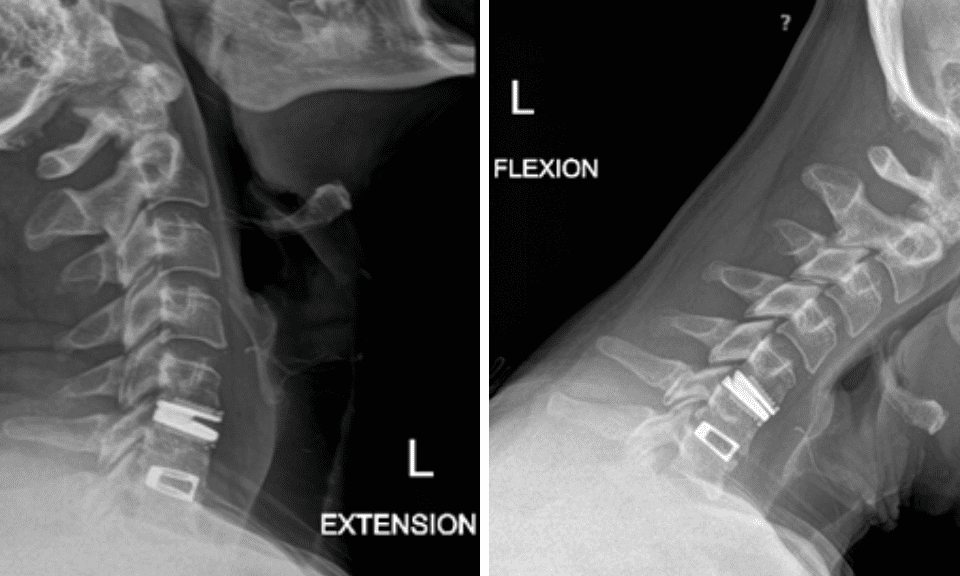

This is a 42-year-old otherwise healthy male who presented electively with progressively worsening neck pain radiating down the left arm, with paresthesia first three digits. He […]